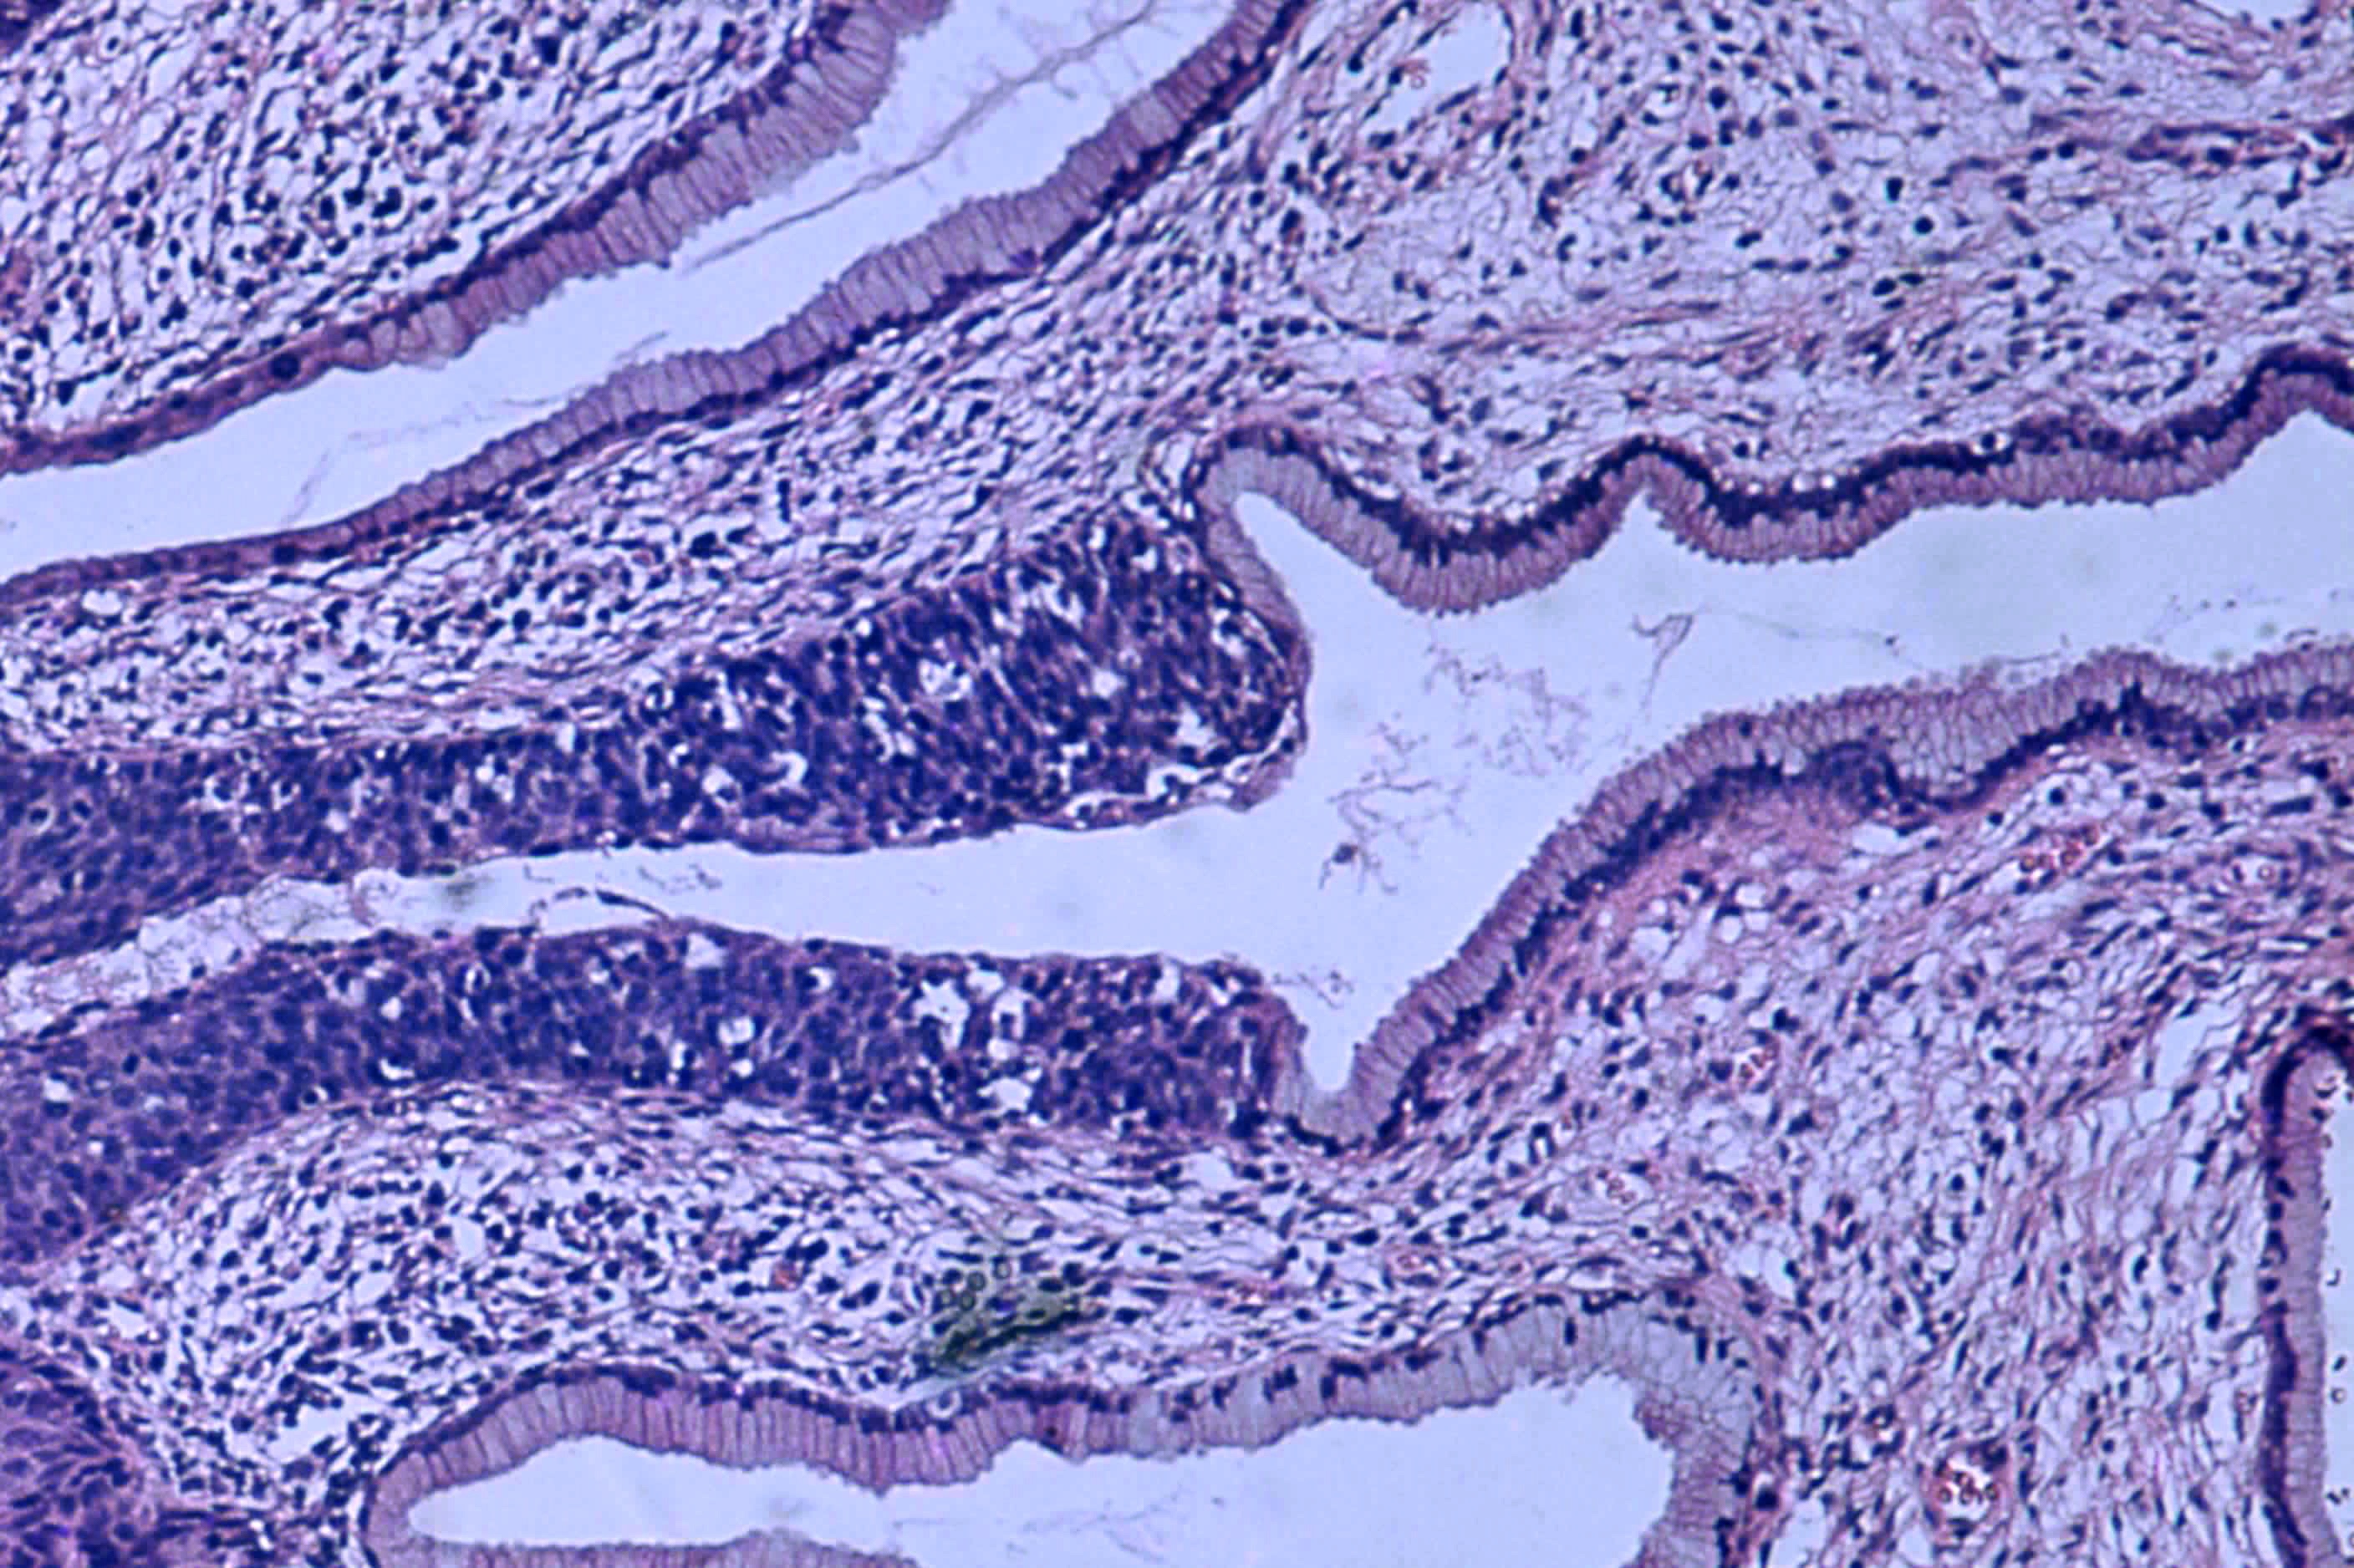

제자리암은 침윤성 암으로 발전하기 전 단계의 암으로, 주변 조직을 침범하지 않고 전이 가능성이 없는 상태를 의미한다. 이형성증의 고등급 병변을 제자리암이라고도 하며, 자궁경부 상피내 종양, 유관 상피내암, 보웬병, 결장 폴립, 고등급 전립샘 상피내 종양, 세기관지 폐포 암종 등이 있다. 제자리암은 외과적 절제, 내시경, 레이저 소작, 방사선 치료 등 다양한 방법으로 제거하여 치료한다.

제자리암은 발생하는 위치에 따라 다양한 종류로 나뉜다. 주요 종류는 다음과 같다.

자궁경부의 편평 상피내 병변(SIL, cervical squamous intraepithelial lesioneng)은 이전 자궁경부 상피내 종양(CIN, cervical intraepithelial neoplasiaeng)으로 불렸으며, 자궁경부암으로 진행될 수 있는 이형성의 한 형태이다. 제자리암이라는 용어는 고등급 SIL과 같은 의미로 사용될 수 있다.[8]